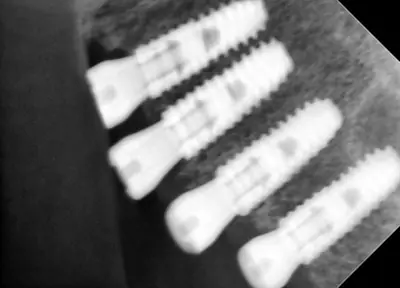

치과 치료를 두려워하는 분들을 위해, 진정요법을 활용한 사례를 소개합니다. 부산에 거주하던 60대 여성 환자가 치아가 많이 손상되어 임플란트와 브릿지 치료를 받았는데, 병원 트라우마와 공포로 어려움이 있었어요. 의식하 진정요법을 통해 깊은 낮잠 같은 상태에서 안전하게 치료를 받았고, 수술 과정도 성공적이었어요. 이 방법은 전신마취보다 안전하고, 환자도 큰 두려움 없이 치료를 마칠 수 있어요. 치과 공포증이 심한 분들도 전문가와 상담 후 진정요법을 고려해보시면 좋겠습니다.